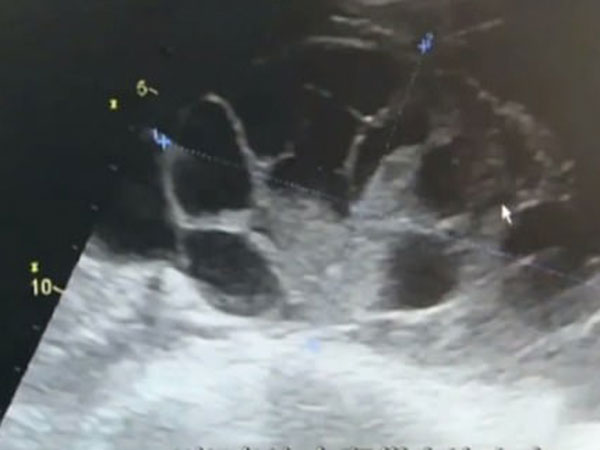

క్రమంగా జరిపిన పరీక్షలలో భాగంగా ఆ మహిళకు ' ఒవేరియన్ హైపర్ స్టిమ్యులేటింగ్ (అండాశయ అధిక ఉద్దీపన) సిండ్రోమ్ ' తలెత్తినట్లు గుర్తించారు. అండం ఎదుగుదలకు అండాశయం ఎక్కువ స్థాయిలో ఉద్దీపన చెందినప్పుడు, అండాల చుట్టూ ద్రవం నిర్మితమవుతున్నప్పుడు ఈ పరిస్థితి కలుగుతుంది.

ఆమె పొత్తికడుపులో సుమారు ఐదు లీటర్ల కన్నా ఎక్కువ ద్రవం పేరుకుని ఉన్నట్లు వైద్యులు గుర్తించారు. అంతేకాకుండా ఆమె అండాశయం 7-8 నెలల గర్భవతిగా ఉన్నట్లుగా విస్తరించింది.